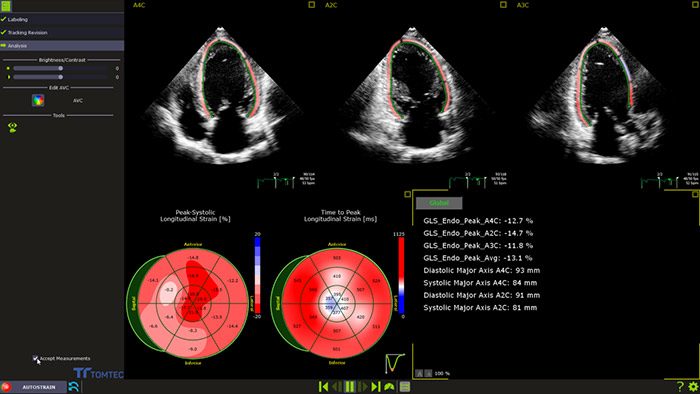

AutoSTRAIN

TOMTEC AutoSTRAIN is een strain-oplossing die werkt met één druk op de knop. De oplossing wordt ondersteund door Auto View Recognition en Auto Contour Placement. De robuustheid is beoordeeld aan de hand van meer dan 6000 beelden. AutoSTRAIN biedt snelle en reproduceerbare GLS-metingen (globale longitudinale strain) van de linker hartkamer binnen de dagelijkse routine.